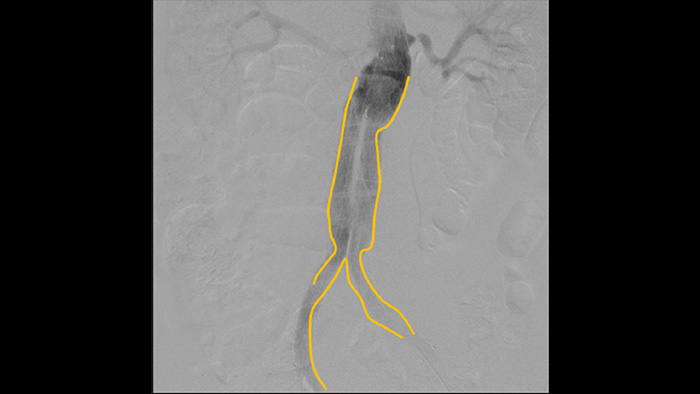

Use the Outlining tool to easily mark a bifurcation or side branches by simply drawing on the monitor of the Mobile Viewing Station with your finger or an externally connected mouse.

Digital subtraction angiography (DSA) is used in interventional vascular procedures to clearly visualise blood vessels by removing structures that can obscure vessel visibility. Roadmap fluoroscopy overlays a previously acquired subtracted contrast image on the live fluoroscopy, allowing you to track a device without reinjecting contrast.